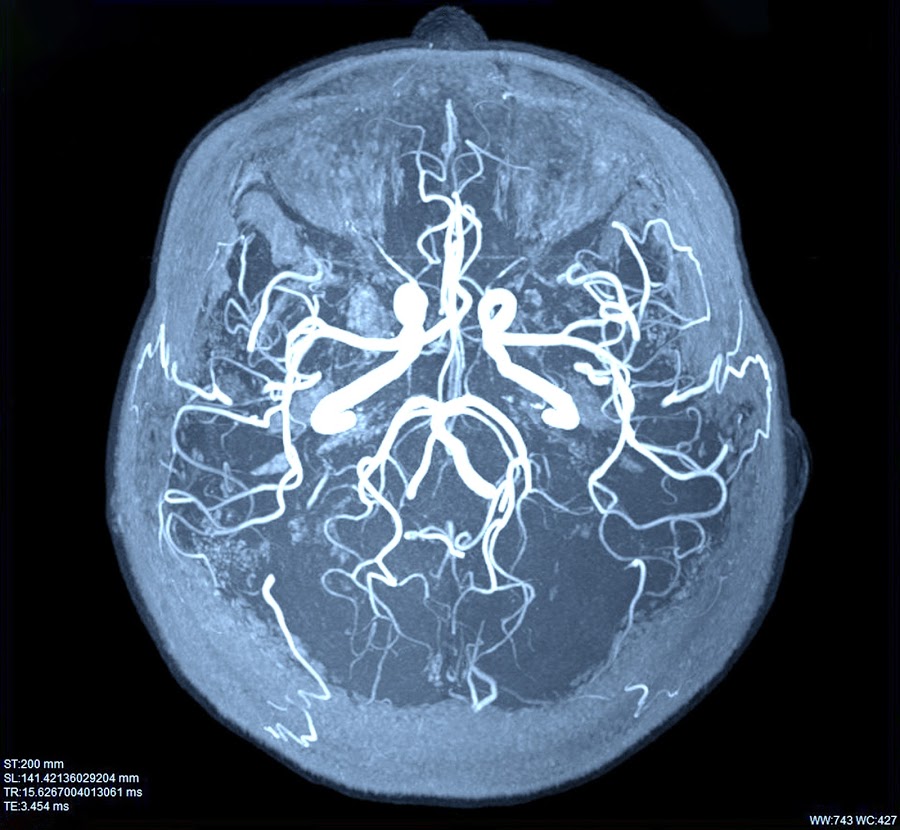

Triệu chứng và những ảnh hưởng lâu dài của chấn thương sọ não

Sọ não là cơ quan quan trọng bảo vệ não bộ, vì thế chấn thương sọ não có thể làm não bộ bị tổn thương và nguy hiểm đến tính mạng nếu không được phát hiện và điều trị kịp thời.